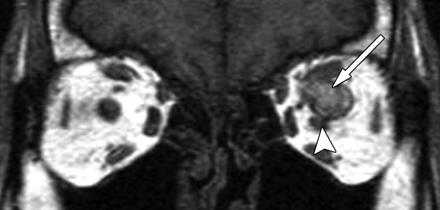

9. Тромбоз верхней глазничной вены.

Корональная Т1-взвешенная МР-томограмма демонстрирует гиперинтенсивный сигнал в проекции расширенной левой верхней глазничной вены (стрелка), свидетельствующий о тромбозе. Маленькая стрелка указывает на смещенный влево зрительный нерв.